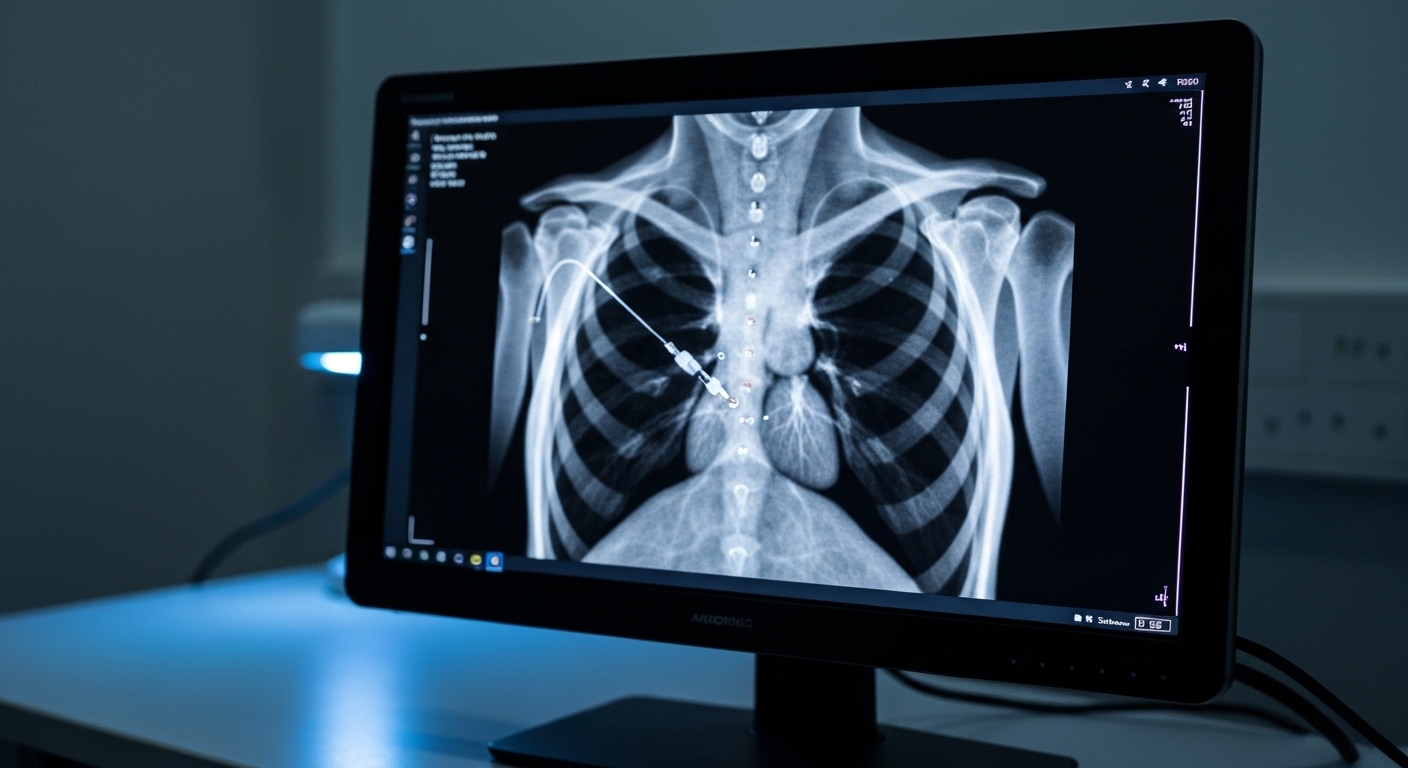

Conventional right ventricular pacing remains the standard of care for bradyarrhythmias, yet its association with electrical and mechanical dyssynchrony often leads to pacing induced cardiomyopathy [1, 2]. This complication affects approximately 12% to 25% of patients with a high pacing burden (defined as a high percentage of ventricular beats initiated by the pacemaker), manifesting as a significant decline in left ventricular ejection fraction and increased heart failure morbidity [2, 3]. While physiological strategies like His bundle pacing have been explored, technical challenges and high lead revision rates have limited their widespread clinical adoption [4, 5]. Consequently, clinicians frequently face the challenge of identifying pacing modalities that preserve cardiac function in patients already predisposed to ventricular dysfunction [6, 3]. The LBBP-FAVOUR trial, a multicenter randomized controlled trial, now provides evidence regarding the clinical efficacy of left bundle branch pacing (a technique that anchors the lead in the left bundle branch area to engage the heart's natural conduction system) in this high risk population.

The LBBP-FAVOUR trial represents the first multicenter, prospective, randomized controlled trial designed to evaluate the clinical efficacy of left bundle branch pacing compared to traditional right ventricular pacing in patients at high risk for cardiac dysfunction. To ensure sufficient statistical power and clinical relevance, the researchers enrolled 160 patients characterized by both a high pacing burden and a high risk of developing pacing induced cardiomyopathy. This specific population is of particular concern to clinicians, as frequent right ventricular stimulation in these individuals often accelerates the progression toward heart failure by inducing an uncoordinated contraction pattern. Following enrollment, participants were randomly assigned in a 1:1 ratio to receive one of the two pacing modalities. This randomization resulted in 80 patients being allocated to the left bundle branch pacing group and 80 patients to the right ventricular pacing group. By utilizing this rigorous prospective design across multiple clinical centers, the study aimed to provide a definitive comparison of how physiological pacing, which directly engages the heart's natural conduction system, affects long term outcomes and ventricular function when compared to the apical or septal stimulation used in right ventricular pacing.